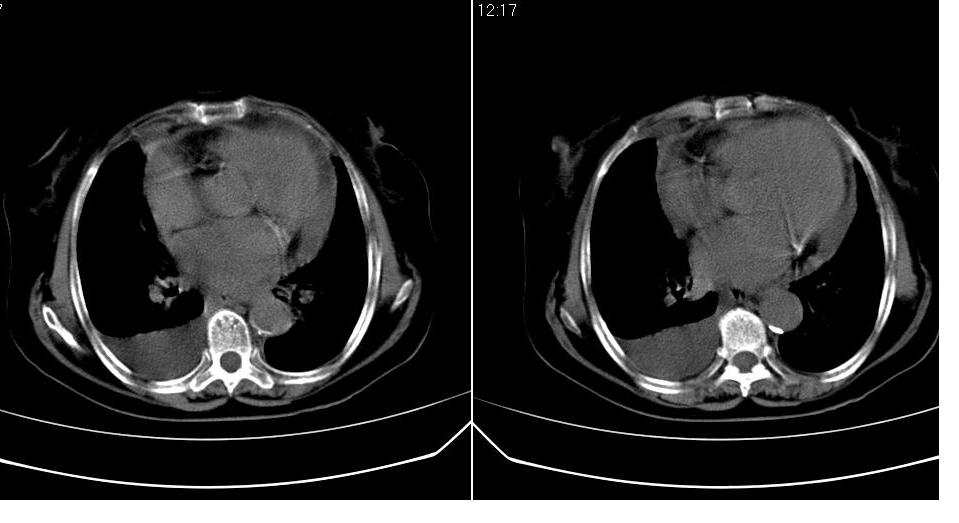

以下是引用liaizhi在2007-7-11 15:41:00的发言:[br]两肺纹理增粗,肺门影增大,气管支气管通畅。升主动脉壁及冠状动脉壁钙化。左房左室稍扩大。心包积液,胸腔积液。考虑冠心病并心功能不全,肺水肿,胸腔积液。

以下是引用zhangzhongshou在2007-7-11 13:16:00的发言:[br]1、冠状动脉钙化[br]2、心包积液[br]3、右侧胸腔积液[br]大家都考虑心衰,冠状动脉钙化、肺纹理增强,胸腔积液、心包积液,表面上是支持,但是为什么右侧有较多积液,左侧没有呢? 如果用结核性胸膜炎,并结核性心包炎也可解释,请楼主进一步提供临床资料。

以下是引用zrs在2007-7-11 14:40:00的发言:[br]支持心衰,心衰所至的胸腔积液常常是右侧多